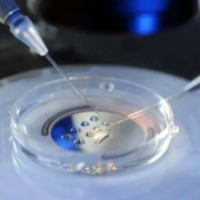

若首次移植后月事自然来潮、子宫内膜厚度达标且内分泌水平正常,最快可在接下来一个周期移植冻胚。但需医生评价认定没有卵子巢过分刺激等合并症。

冻胚移植:若有冻存胚胎,3个月后复查子宫腔内环境,达标便可重启。

3. 制订化方案:根据失败缘故(如胚胎质量差、内膜容受性低)整合药物或技术(如PGT胚胎检查筛选)。